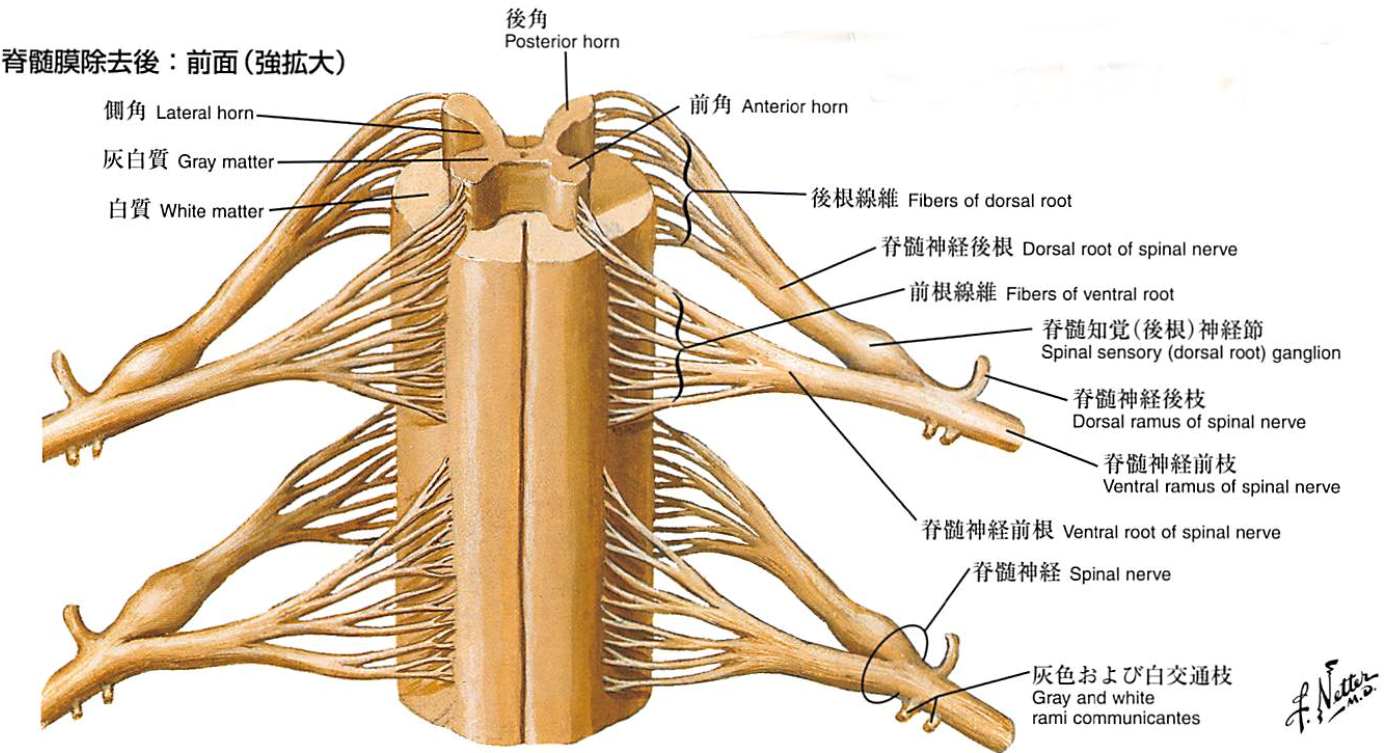

エキスパートのための脊椎脊髄疾患のMRI 第3版 | 柳下 章, 相田, 脊髄・脊椎疾患 | 名古屋大学大学院医学系研究科 脳神経外科学,

脊髄・脊椎疾患 | 名古屋大学大学院医学系研究科 脳神経外科学, 頚椎脊柱管狭窄症の症例と症状について|白石脊椎クリニック,

腰椎変性疾患 | 総合東京病院【公式】中野区 練馬区 24時間救急受入, 脊椎脊髄疾患について・主な疾患 | 一般社団法人 日本脊椎脊髄病,

脊椎脊髄疾患について・主な疾患 | 一般社団法人 日本脊椎脊髄病, 腰痛という非特異的症状で発症した特発性後脊髄動脈領域の脊髄,